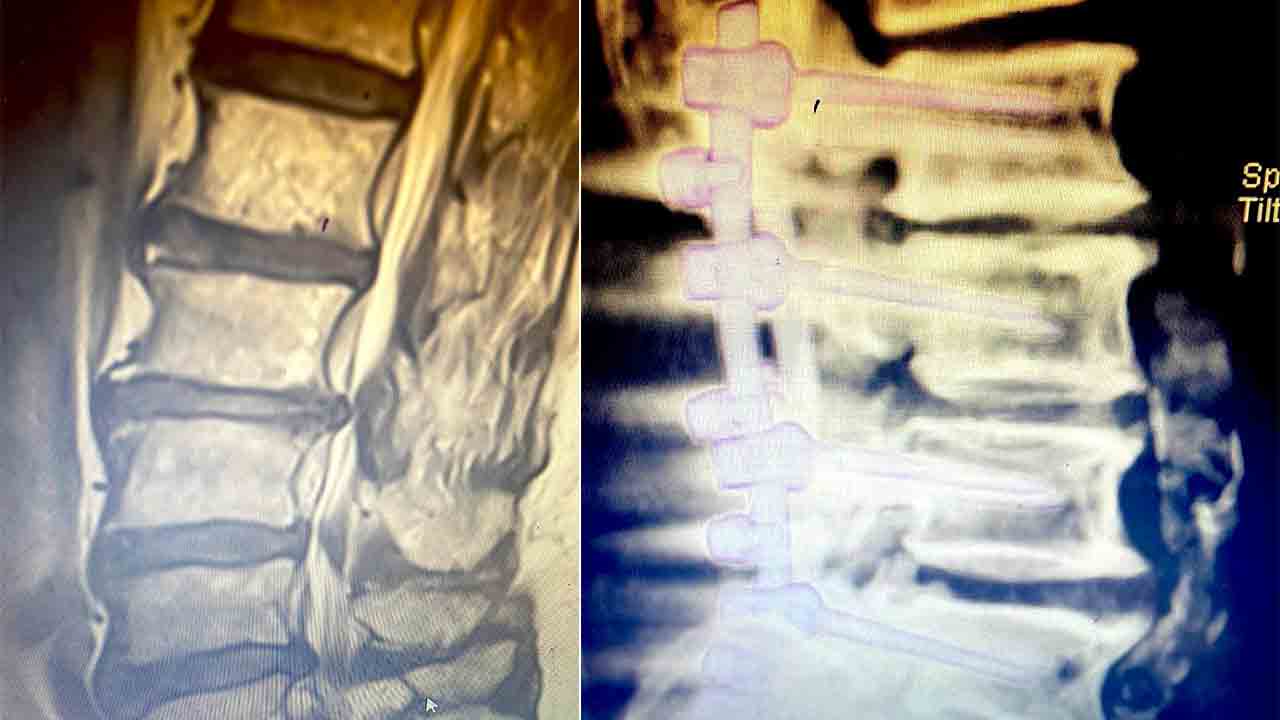

Operasyon hakkında bilgi veren Op. Dr. Serkan Zengin, “Cerrahi tedavide kişinin hastalık seviyesine göre bir operasyon planlanmaktadır. Farklı seviyelerde sıkışma ve kemik daralması varsa büyüyen kemik dokusu küçültülür, omurga kanal çapı genişletilerek sıkışan sinirlerin üzerindeki baskı azaltılır ve vidalarla omurga sabitlenir. Platin vidalar ameliyattan sonra 6 hafta süre içerisinde kemik ile kaynaşmaktadır. Böylece omurga taşıyıcı işlemine de devam edebilir. Ameliyattan sonra, genellikle hasta 2 gün içerisinde taburcu edilir. Operasyon sonrasında beli zorlayıcı hareketlerden ağır kaldırmaktan ve darbelerden hastanın kendini koruması gerekmektedir” dedi. Ameliyat esnasında hastaya yüksek teknolojiden faydalanarak navigasyon ile vida atılabildiğini kaydeden Zengin, “Operasyon esnasında tomografi çekilerek kontrol mekanizmamız ameliyathanede tamamlanmaktadır. Bu yüksek teknoloji ve deneyimli eller ile birlikte komplikasyon riskini sıfıra yakın bir seviyeye indirebilmektedir” diye konuştu.